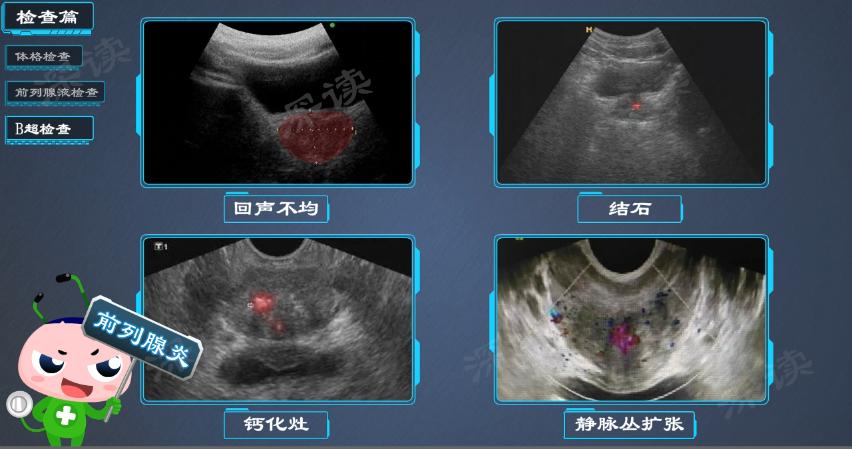

B超检查

B超检查能够清楚地观察到前列腺的组织形态和结构等情况。

如果B超检查发现前列腺回声不均匀、存在结石或钙化灶、周围静脉丛扩张时,可以帮助诊断前列腺炎。